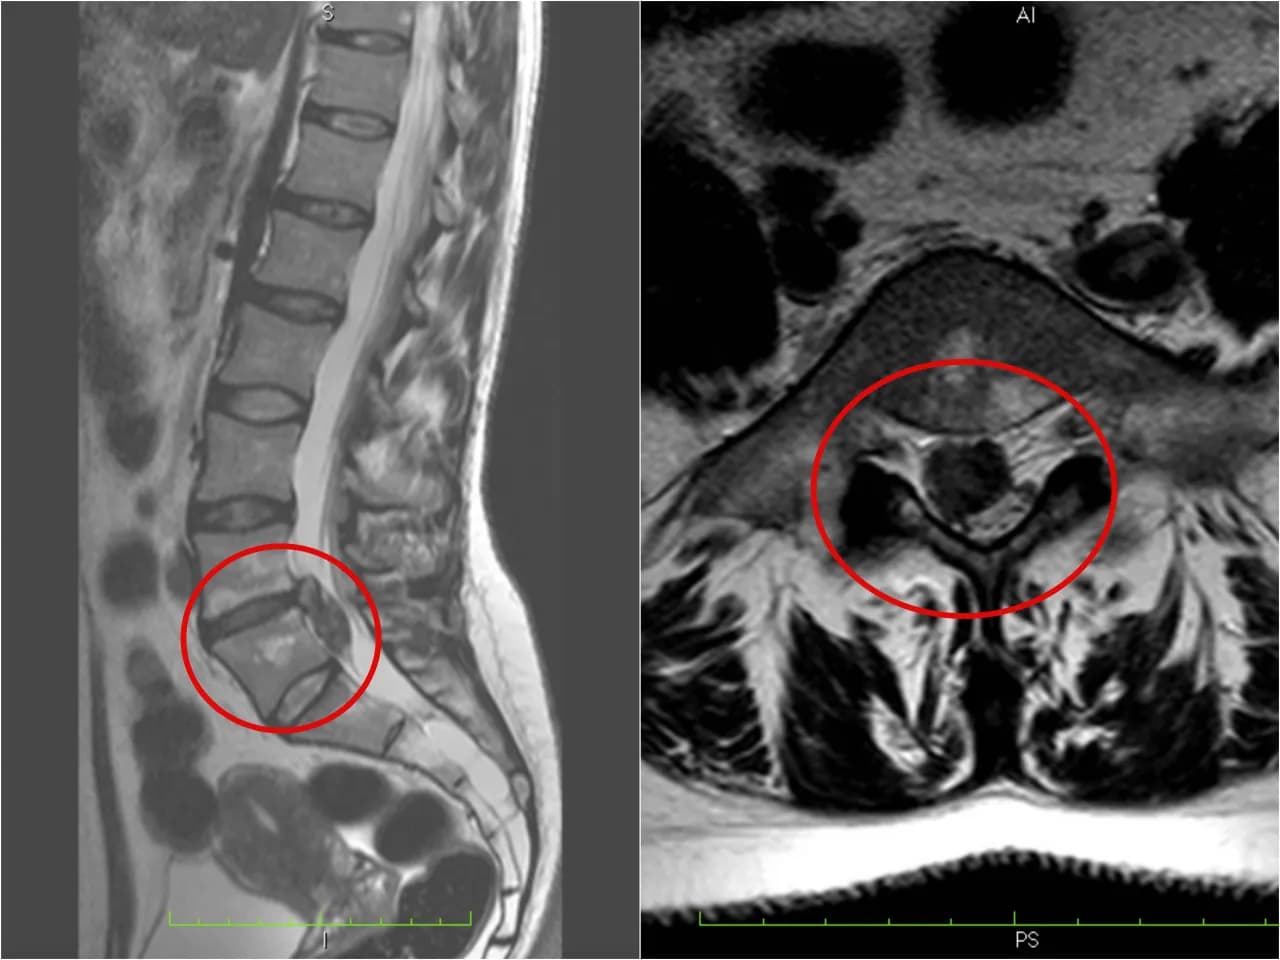

Diagnostyka wypukliny obejmuje badanie fizykalne oraz obrazowanie. Rezonans magnetyczny (MRI) jest najskuteczniejszą metodą, pozwalającą dokładnie ocenić stan krążków międzykręgowych. Czasem stosuje się również tomografię komputerową (CT) lub badanie rentgenowskie.